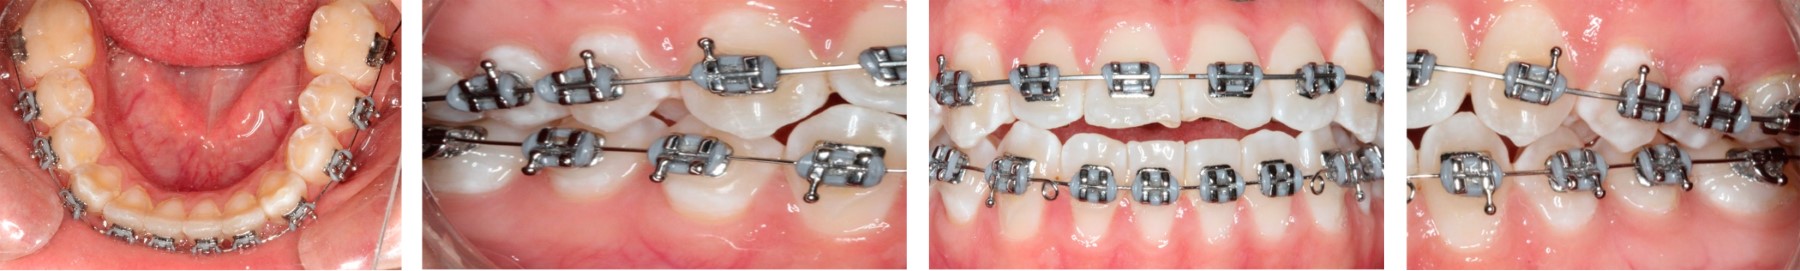

A los siete meses, una vez obtenido el espacio suficiente, se incorporó al arco el incisivo lateral superior izquierdo. A los 10 meses de tratamiento empezó la formación del segmento anterior superior y se completó la aparatología fija en arcada inferior. Se realizó desgaste interproximal para iniciar fase de alineación y nivelación en la arcada inferior. Se decidió colocar recordatorios palatinos en los incisivos superiores con el objetivo de evitar mordida abierta por proyección lingual (Figura 5).

Una vez terminada la alineación y nivelación en ambas arcadas fue necesario tomar una radiografía panorámica y modelos de control para evaluar el paralelismo radicular. Después de recolocar los brackets se reniveló con arcos rectangulares 0.017" × 0.025" de nitinol. Posteriormente, se colocaron arcos de acero inoxidable 0.017" × 0.025" y se terminó asentando la mordida con elásticos clase III de 5/16" con una fuerza de 4.5 oz en conjunto con elásticos triangulares 3/16" 6 oz en los segmentos anteriores (Figura 6).

Figura 5

Figura 6